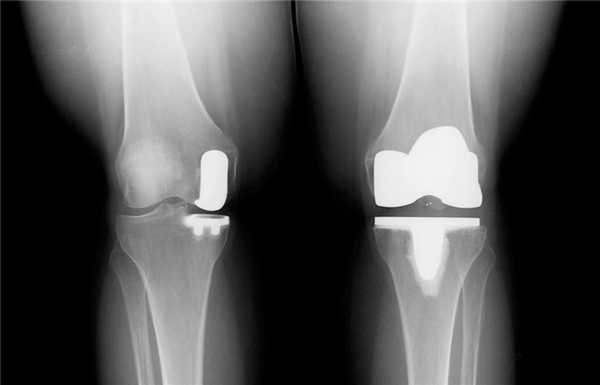

Сравнение двух типов операций.

Две техники операции у одного пациента.